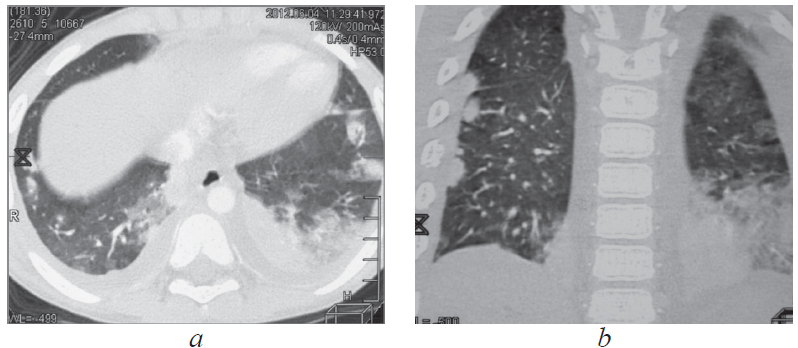

Анамнез заболевания. В процессе диспансерного наблюдения по туберкулезному контакту, в связи с положительной пробой с аллергеном туберкулезным рекомбинантным, проведена впервые мультиспиральная компьютерная томография (МСКТ) органов грудной полости 22.08.2011 (рис. 1) с внутривенным контрастированием. Заключение: «В легких без очаговых и инфильтративных изменений. Выявляются лимфоузлы трахеобронхиальной группы справа (до 8 мм), трахеобронхиальной группы слева (до 7 мм), лимфатические узлы корней легких с двух сторон (до 6 мм), бифуркационной группы (до 7 мм). В структуре лимфатических узлов корней легких и вдоль промежуточного бронха множественные кальцинаты».

Рис. 1. Пациент, 5 лет. Компьютерная томография грудной клетки (туберкулез внутригрудных лимфоузлов) от 22.08.2011

Fig. 1. Patient, 5 years old. Computed tomography of the chest (tuberculosis of the intrathoracic lymph nodes), 22.08.2011